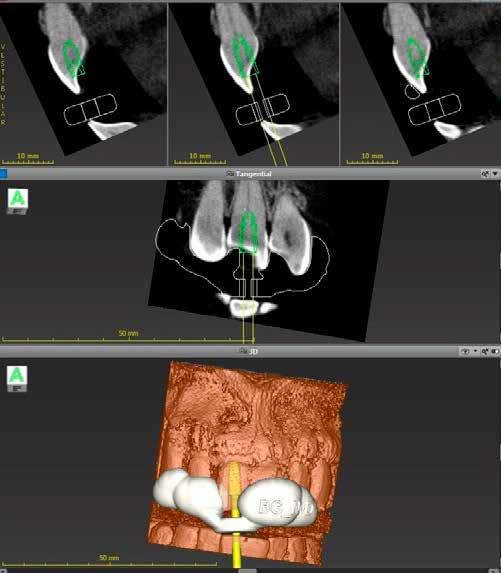

A 28 éves hölgy pácienst az eddig fel nem lelt második mesio-bukkális (MB2) gyökércsatorna lokalizálása és a kérdéses fog endodonciai ellátása miatt utalták dr. Karaś rendelőjébe. A fog panaszos volt (jobb felső első nagyőrlő; 16) és kezelést igényelt. A mesialis gyökércsatorna vizsgálata, valamint a kezelés megtervezése céljából CBCT-felvétel készült. A gyökér alakja és a gyökérhártyarés kiszélesedése alapján különálló gyökércsatorna bemeneti nyílást és önálló foramen apicale-t vélelmeztünk az MB2 csatorna számára. Egy axiális irányú szeleten a mesio bukkális gyökér palatinális részén egy keskeny önálló csatornaszakaszt észleltünk, amely tovább erősítette az önálló MB2 csatorna fennállásának valószínűségét. Gyulladásra utaló jeleket észleltünk a mesio-, és diszto-bukkális gyökerek gyökércsúcsánál, valamint az azonos oldali arcüregben (1. a–c ábra).

A mesialis gyökér megfelelő endodonciai ellátásának ellen őrzése céljából a pácienst egy kontroll CBCT-felvételre irányítottuk. A felvételen látható volt, hogy az MB2 csatornát teljes terjedelmében ki tudtuk tölteni a sealerrel, továbbá, hogy az apikális harmadban az MB1 és MB2 csatornák között egy keskeny összeköttetés található, valamint hogy az MB1 és MB2 gyökércsatorna különálló végződéssel rendelkezik (14. ábra) . A fogat kompozitfelépítéssel láttuk el, majd visszairányítottuk a beküldő orvosához. Csücsökborítást biztosító indirekt restaurátum készítését javasoltuk, illetve 6 hónap múlva kontrollvizsgálat céljából visszarendeltük magunkhoz. A 6 hónapos kontroll során készített CBCT-felvételen a gyökércsúcsok körül nem voltak gyulladásra utaló jelek. A fog teljesen panaszmentes volt és a Schneider membrán megvastagodását sem észleltük (15. a–b ábra.).